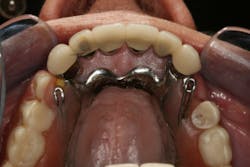

This clinical case began with a frustrated 75-year-old patient, who, after many years of failed attempts to repair the functional problem, came to the realization that a different solution was in order. The existing problem of an upper removable precision attachment partial denture was addressed first. The issue at hand was that the partial denture was perforated at the precision attachments, with the upper left side being more significant compared to the right side (figures 1–5). As a result, retention was adequate on the right side, but limited on the left. The patient was also concerned about esthetics, but needed a solution that kept a restricted budget in mind.

Dentition: Upper anterior splinted crowns had open margins and caries. Radiographs confirm decay, along with open margins (figures 6–11). Lower incisal anterior wear noted (figure 2).